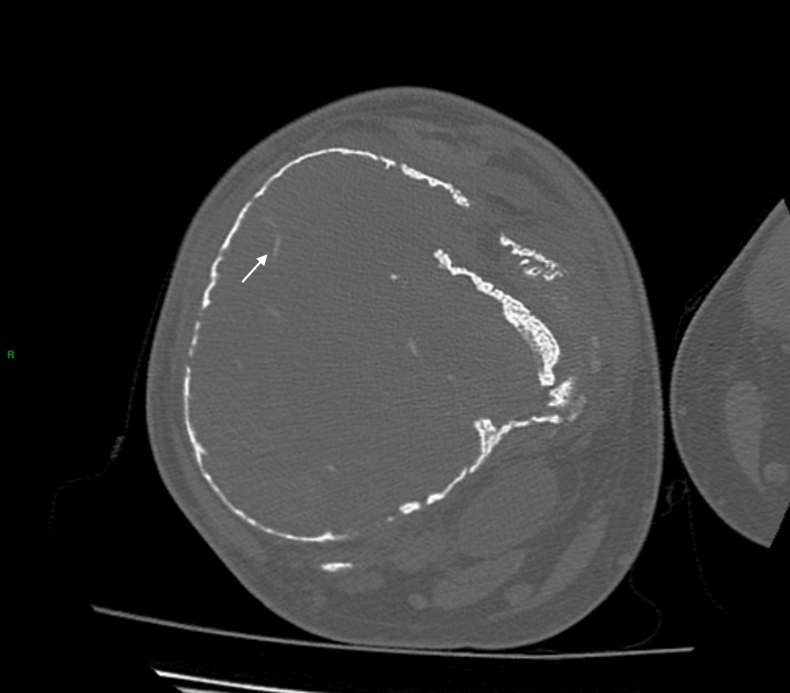

影像学检查方面,横轴位平扫CT(图1)呈现股骨远端有分叶状溶骨性病变,且伴有骨内膜扇形、皮质破裂以及软骨样基质钙化的多个病灶,呈现出“环形和弧形”模式;矢状位CT(图2)则显示病变从远端干骺端延伸至骨骺端,存在皮质变薄和局灶性皮质破裂。

图1